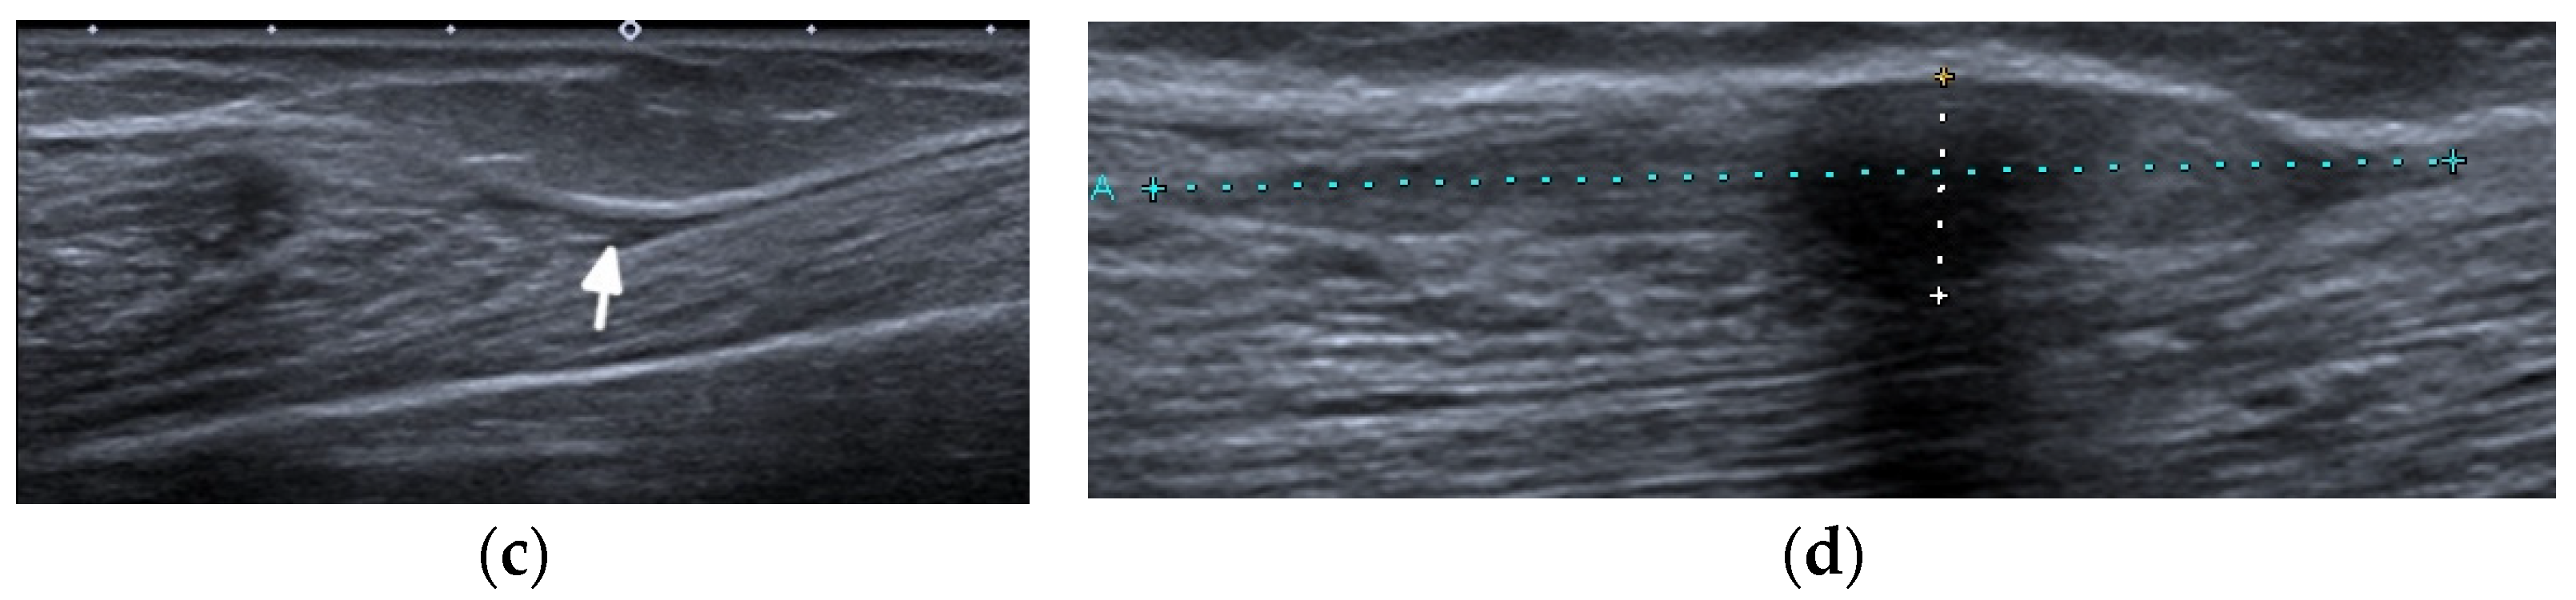

MRI is the most appropriate modality for the evaluation of muscle involvement, despite its low specificity, and US plays a complementary role [1,19] (Figure 9). MRI is used in the differential diagnosis and as a follow-up to a therapeutic response, and is useful to define the biopsy site [1,19]. Fat-saturated, fluid-sensitive MR sequences with long time until echo recovery are the most sensitive for identifying acute inflammation, manifesting as areas of high signals within the muscle [19]. Inflamed muscles also demonstrate contrast enhancement (Figure 9). In the chronic phase, involved muscles may undergo fatty infiltration with or without a loss of muscle bulk. These are seen on MRIs on T1-weighted sequences as areas of high signal intensity, replacing the normal intermediate signal of muscle fibers [19].

Figure 9.

Magnetic resonance (MR) imaging of lower legs of a 34-year-old male with systemic lupus erythematosus with myositis. (a) Coronal T2 turbo inversion recovery magnitude and (b) axial postcontrast T1-weighted MR images with fat saturation show increased signals in the muscles of the lower left leg (arrows), especially peroneus brevis and the lateral head of gastrocnemius, and to a lesser extent, soleus musculature, with heterogeneous enhancement in (b) after the administration of a gadolinium base contrast agent. In (a), note the subcutaneous edema around the left lower leg (arrowhead).

US may assist with the diagnosis and characterization of disease activity in inflammatory myopathies, with reported 82.9% sensitivity for detecting histologically proven myositis [17]. Inflammation and edema cause patchy or diffusely increased echogenicity of muscles, which may also appear swollen [17,19]. Increased vascularity on power Doppler may be seen [19]. In chronic diseases, the muscles appear atrophic with reduced volume and further increased echogenicity due to the progressive infiltration of fatty tissue [1,17,19]. In addition, by shear-wave elastography (SWE), US is able to evaluate muscle stiffness [20]. Di Matteo et al. [20] performed SWE on the quadriceps muscles in 30 SLE patients (without previous/current myositis or neuromuscular disorders) as well as 15 healthy subjects that matched the patients in age, sex, and BMI. SWE was significantly lower in SLE patients compared with the healthy subjects (1.5 m/s vs. 1.6 m/s respectively, p = 0.01).